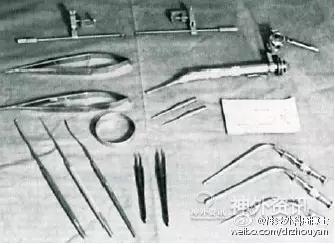

随着手术显微镜的应用,相配套的显微手术器械也得到了发展。(图10、11)其中尤为重要的是双极电凝的发明和使用,有两个功臣James Greenwood和Leonard Malis。

1964年,Kurze在其开创性论著《神经外科的显微技术》中展示了显微外科设备。

适用于神经外科的Malis双极电凝。